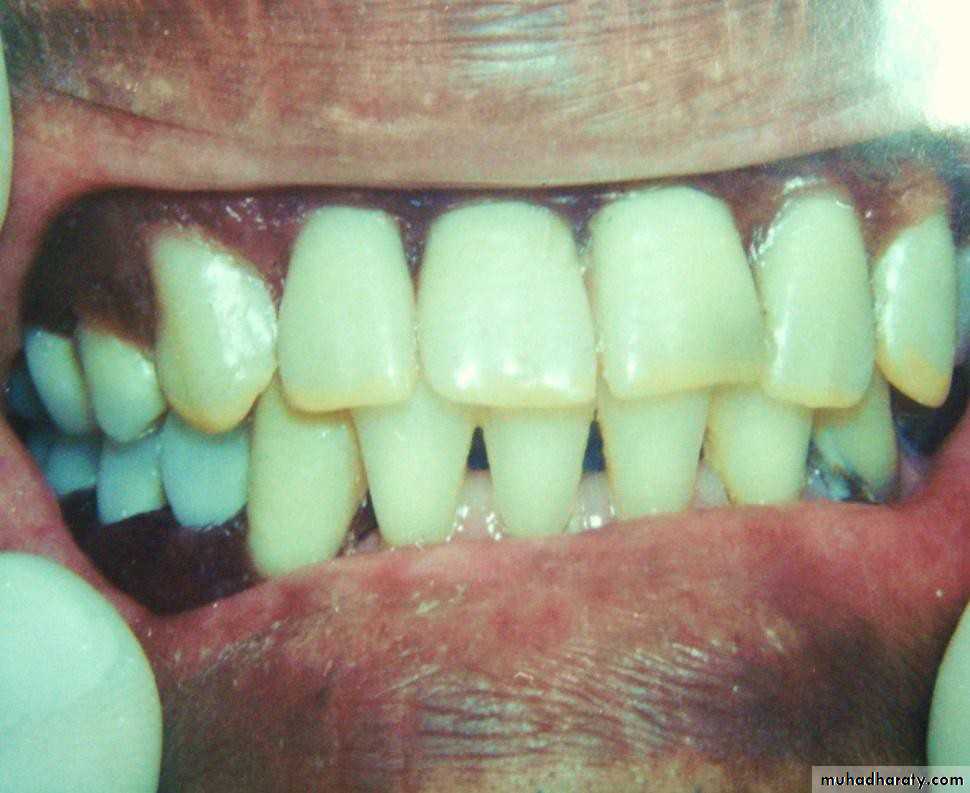

• 1- Simple tooth modification of vital abutment.

• A- Thimble-shaped

• coping• 2- Tooth reduction and cast coping of vital abutment

• B- Tooth reduction• and cast coping

• 2- Tooth reduction and cast coping of vital abutment